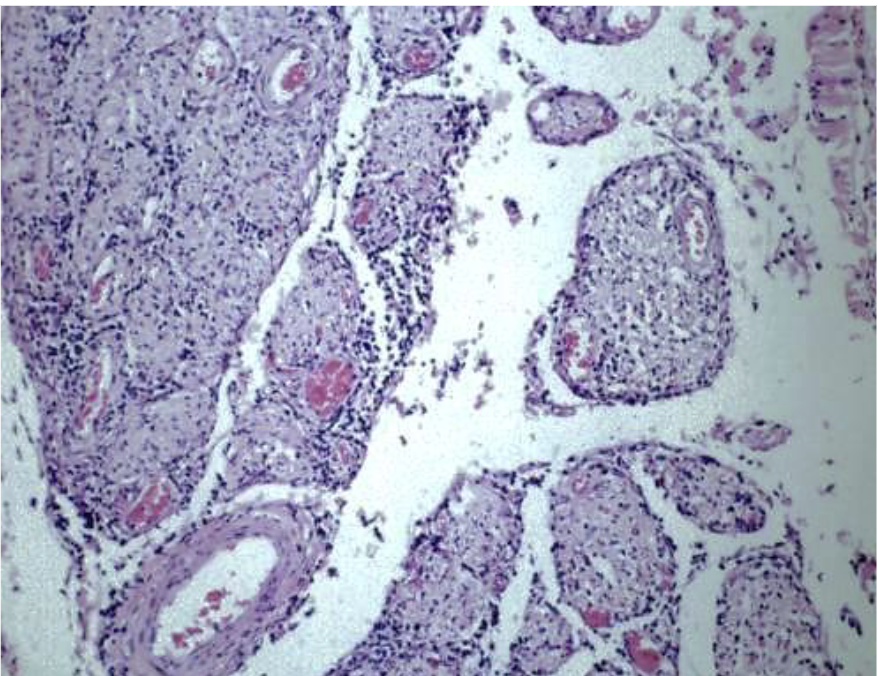

Cauda Equina Neuritis (Cauda Equina syndrome) in horses: Possible immune-mediated etiology

Lymphocytic infiltration of nerve roots,

Case from JPC collection.

Lymphocytes and plasma cells –> inflammatory conditions